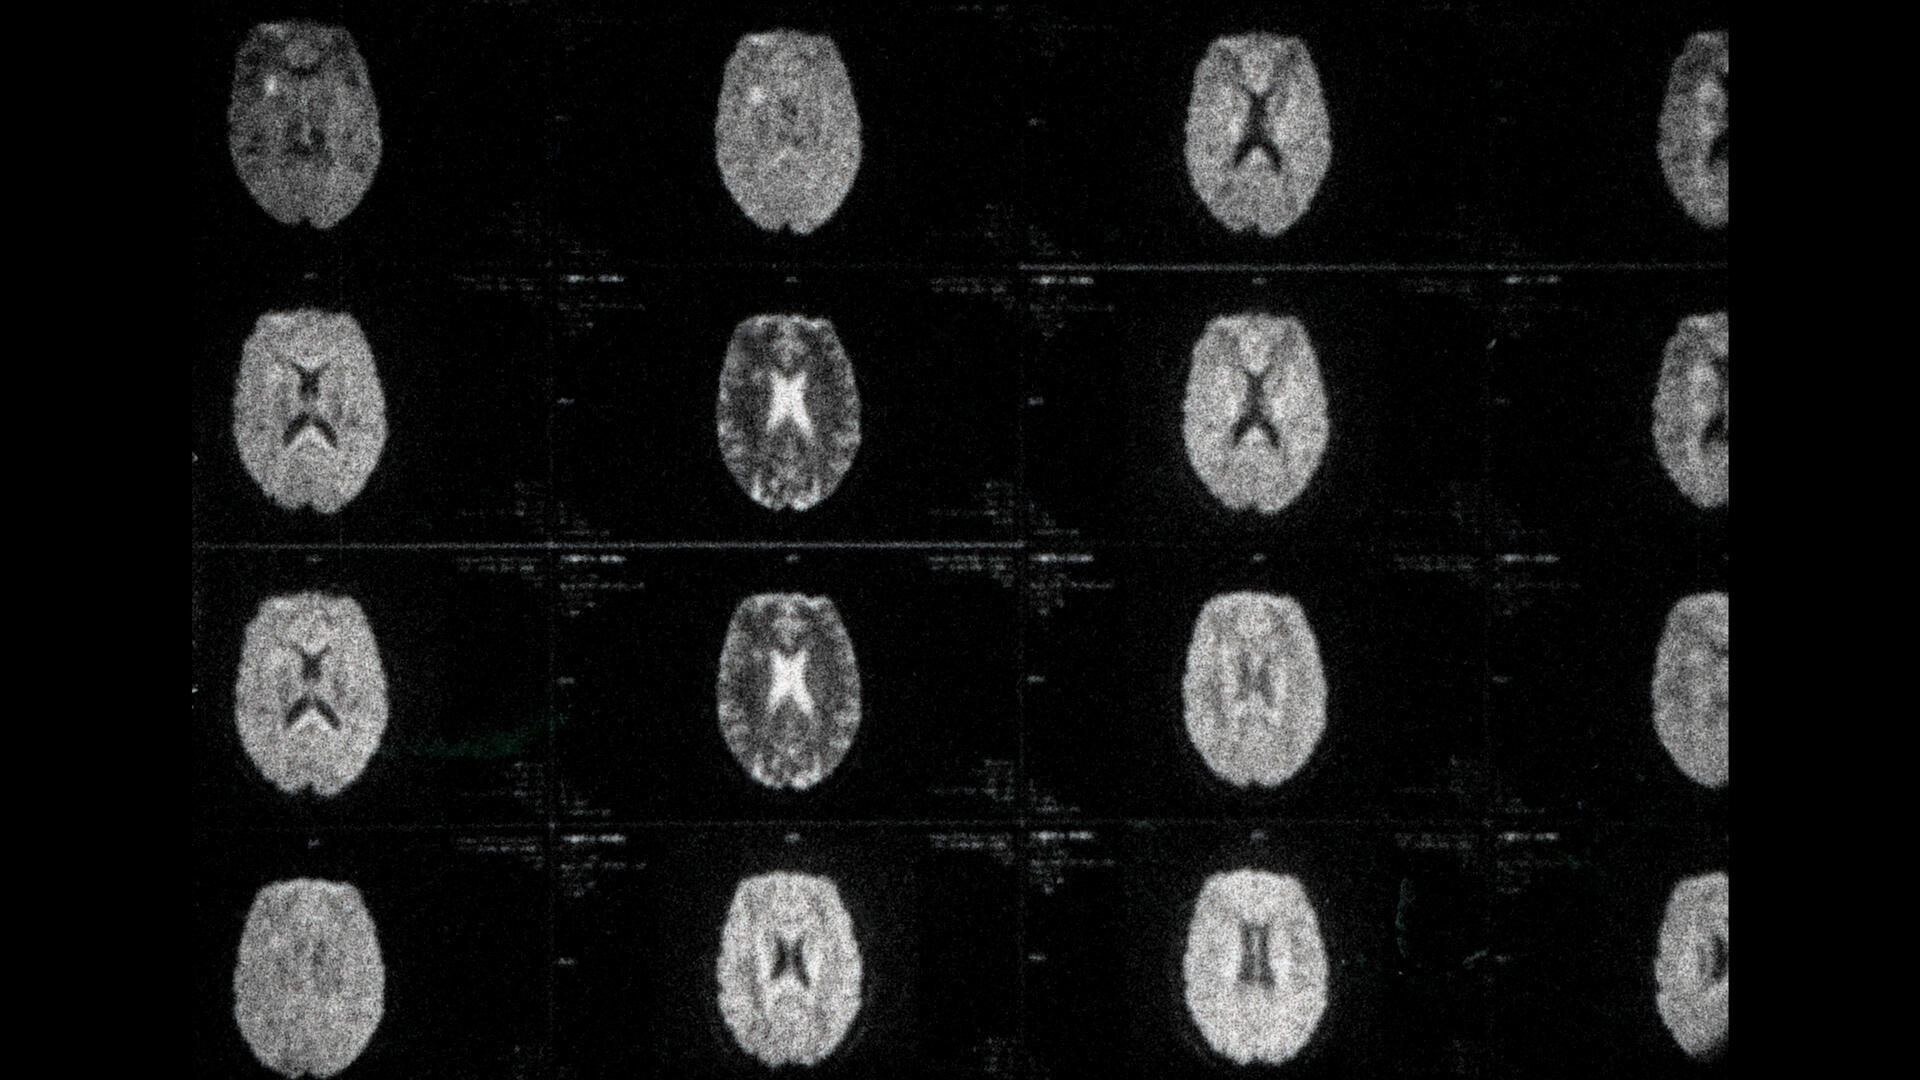

Dans ma tête est un court-métrage expérimental à la première personne qui traite de la sclérose en plaques de la cinéaste à travers ses images de résonance magnétique.